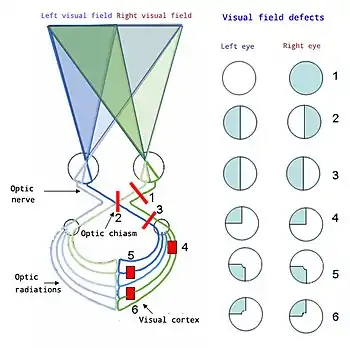

Optic chiasm

The optic nerves from both eyes meet and cross at the optic chiasm,[34][35] at the base of the hypothalamus of the brain. At this point, the information coming from both eyes is combined and then splits according to the visual field. The corresponding halves of the field of view (right and left) are sent to the left and right halves of the brain, respectively, to be processed. That is, the right side of primary visual cortex deals with the left half of the field of view from both eyes, and similarly for the left brain.[32] A small region in the center of the field of view is processed redundantly by both halves of the brain.

According to Pollock et al. (2010) stroke is the main cause of specific visual impairment, most frequently visual field loss (homonymous hemianopia, a visual field defect). Nevertheless, evidence for the efficacy of cost-effective interventions aimed at these visual field defects is still inconsistent.[54]

From top to bottom:

1. Complete loss of vision, right eye

2. Bitemporal hemianopia

3. Homonymous hemianopsia

4. Quadrantanopia

5&6. Quadrantanopia with macular sparing

Proper function of the visual system is required for sensing, processing, and understanding the surrounding environment. Difficulty in sensing, processing and understanding light input has the potential to adversely impact an individual's ability to communicate, learn and effectively complete routine tasks on a daily basis.

Homonymous hemianopia is a type of blindness that destroys one entire side of the visual field typically caused by injury in the primary visual cortex.

Quadrantanopia is a type of blindness that destroys only a part of the visual field typically caused by partial injury in the primary visual cortex. This is very similar to homonymous hemianopia, but to a lesser degree.